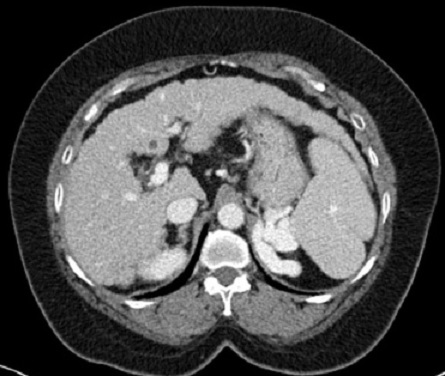

Aspect radiologique TDM de la

cirrhose du foie phase veineuse : Le bord du foie

est irregulier , atrophique , veine porte est dilate

et splenomegalie |

Même cas en coupe a

inferieure de la bifurcation portale : Dilatation de

la veine porte et veine splenique . |